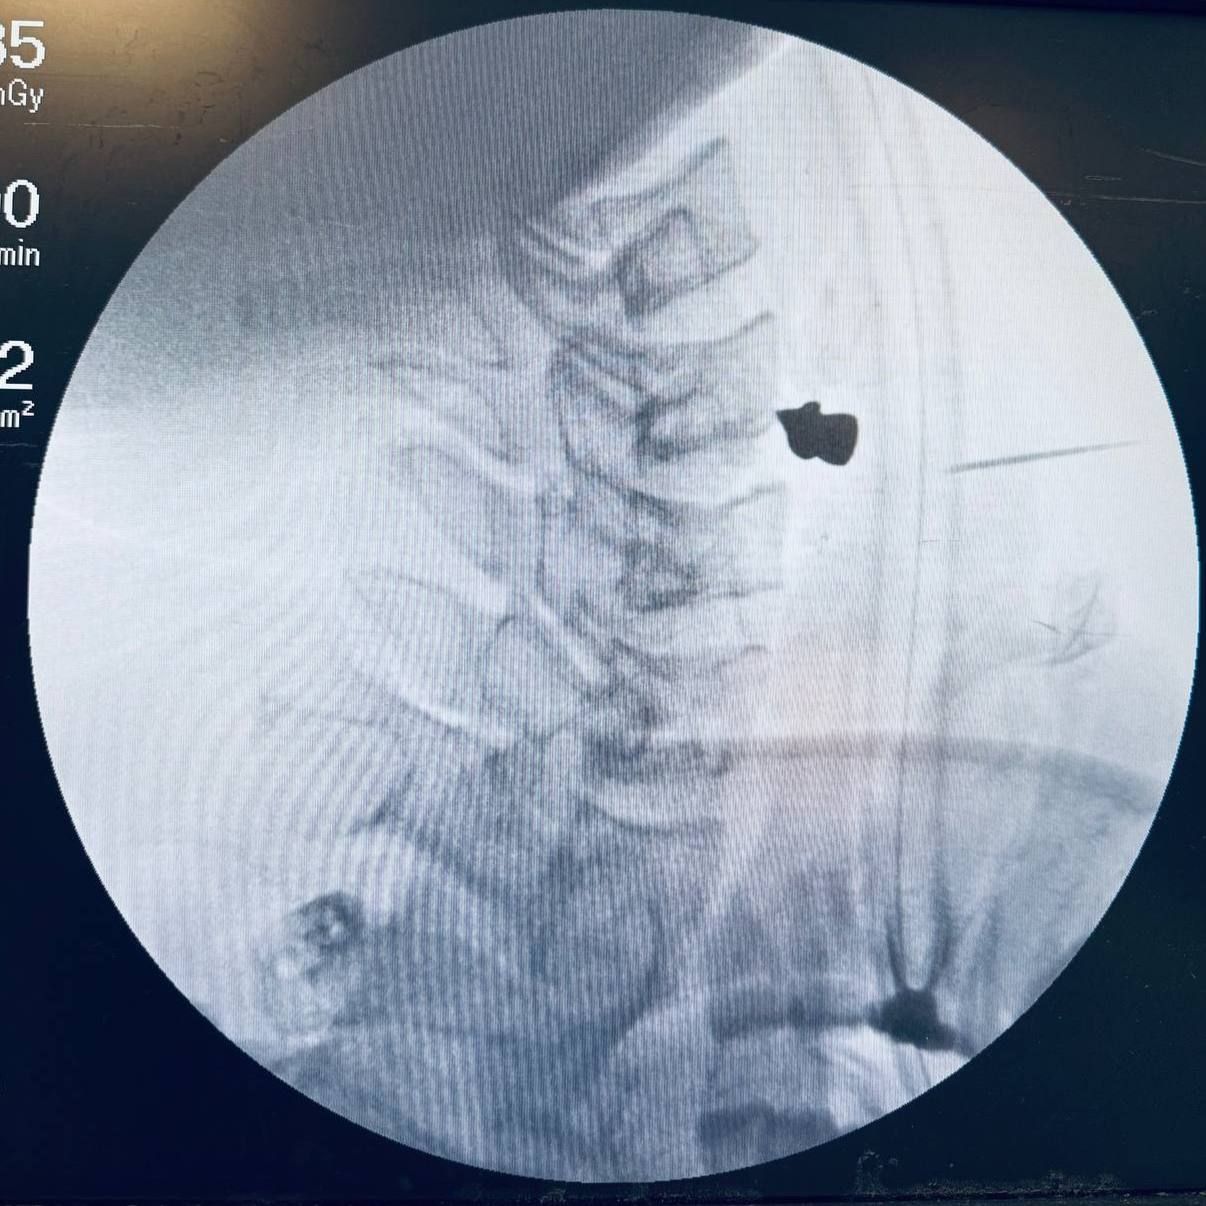

Бедняге было трудно глотать и говорить. КТ показало, что ни артерии, ни трахея, ни пищевод задеты не были – пуля чудом прошла через шею и встала в позвоночнике. Пациента срочно повезли на операцию. Пулю вытащили за 20 минут, парень всё еще в больнице, приходит в себя.